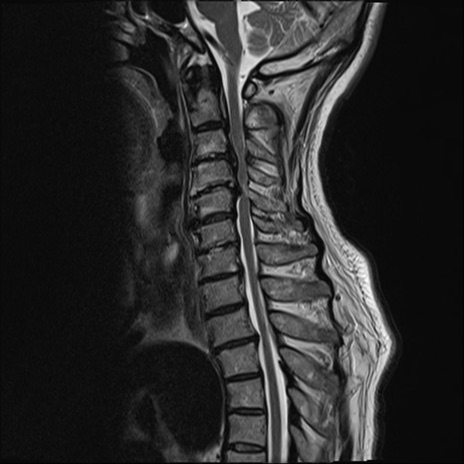

【整形】TIPS症例7 頚椎MRI T2WI(矢状断像)

頚椎MRI

T1WI(矢状断像)

矢状断像と横断像